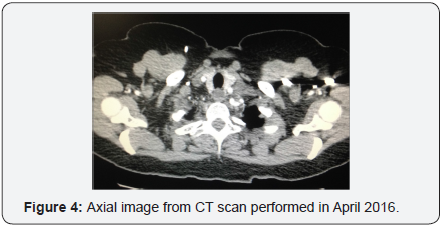

In October 2015 a PET scan revealed pulmonary parenchymal metastasis, left axillary adenopathy and left cervical adenopathy lateral to the thyroid gland. Tumor marker CA 125 was increased to 40 units per milliliter, a significant elevation above the normal threshold (<35U/mL). Left supraclavicular lymph node FNA confirmed metastatic recurrence of carcinosarcoma. The patient received 4 cycles of carboplatin/paclitaxel chemotherapy in November 2015. PET scan in February 2016 demonstrated good response to treatment, follow up CT in April 2016 did not reveal any masses, (Figure 4).